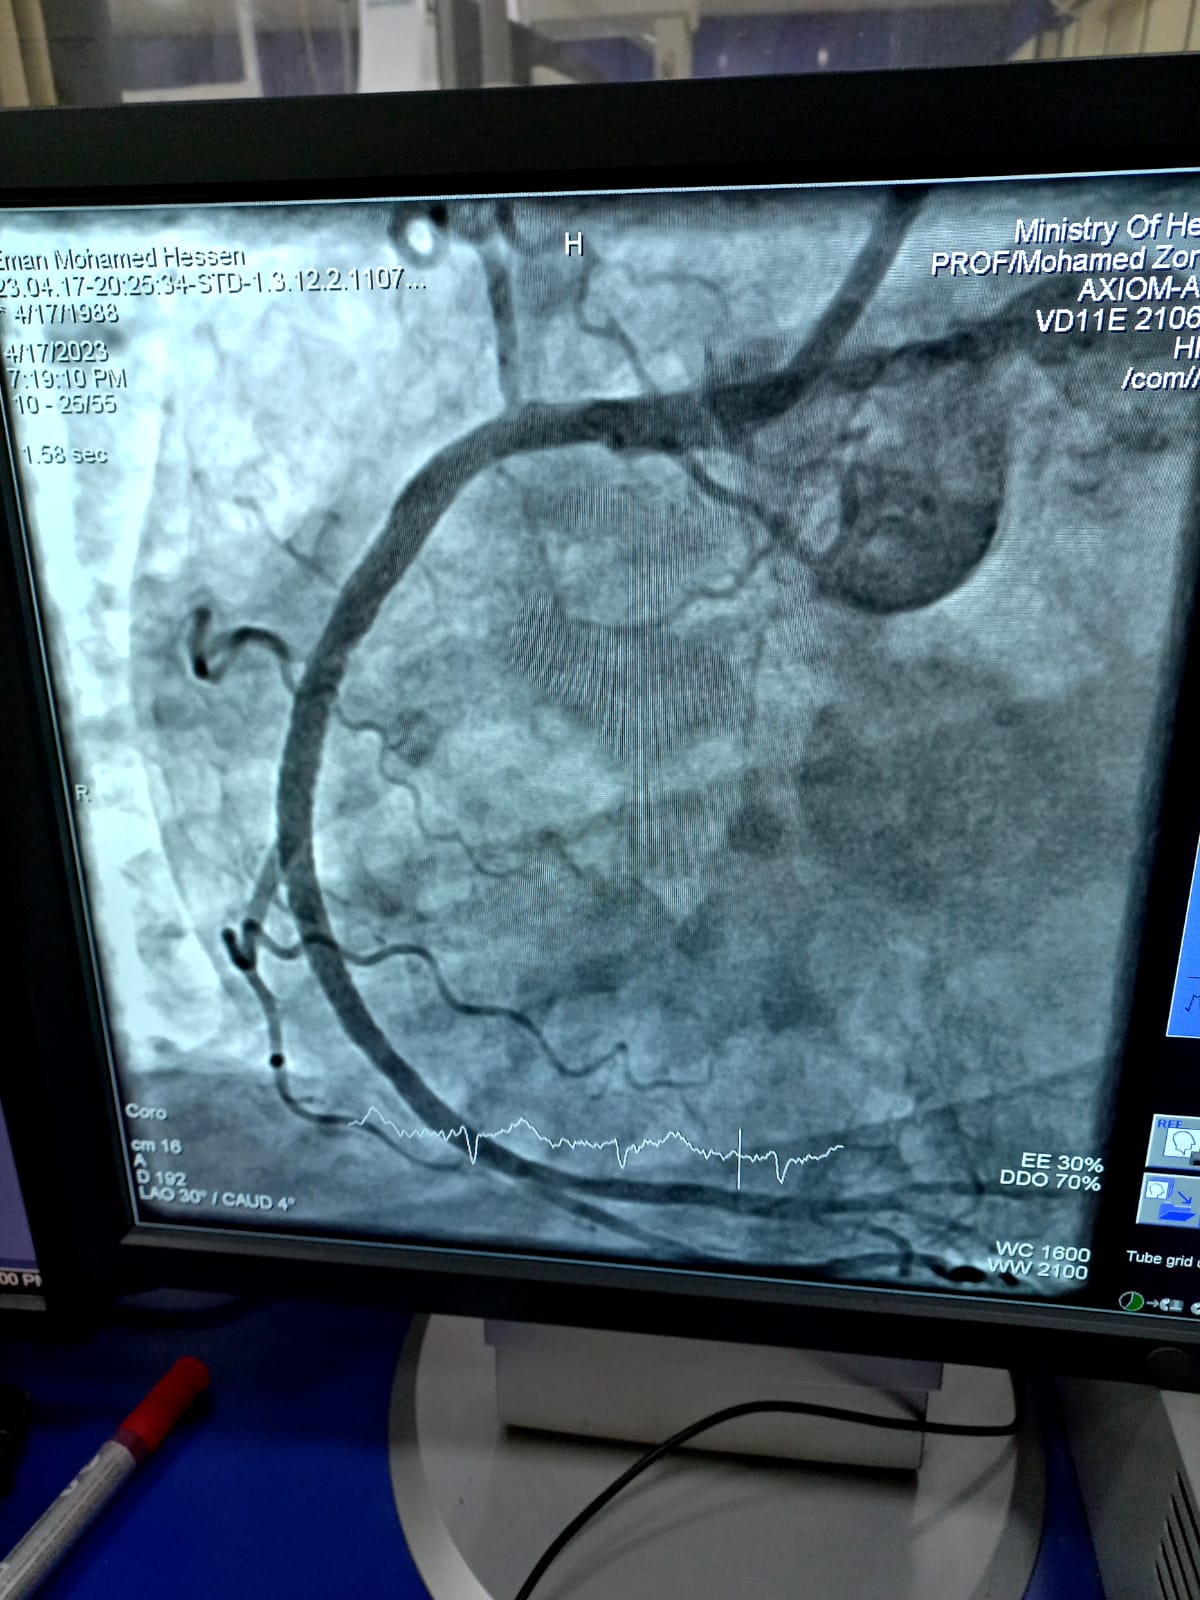

تنفيذاً لتوجيهات الدكتور خالد عبدالغفار وزير الصحة والسكان، والأستاذ الدكتور ممدوح غراب محافظ الشرقية، تعليمات الدكتور هشام شوقي مسعود وكيل وزارة الصحة بالشرقية، برفع كفاءة الخدمات الطبية المقدمة للمرضى بمستشفيات الصحة بالمحافظة، استمرارا لنجاح منظومة العلاج علي نفقة الدولة، قام الفريق الطبي بوحدة القسطرة القلبية بمستشفى الزقازيق العام، بقيادة الأستاذ الدكتور السيد فرج أستاذ القلب والمشرف الفني للقسطرة القلبية، والدكتور حسام عطية استشاري القلب ومدير وحدة القسطرة، والدكتور محمد عبدالله، والدكتور عبدالله بنداري أطباء القلب، بإجراء قسطرة قلبية عاجلة لإنقاذ حياة مريضة تبلغ من العمر ٣٥ عاماً، كانت تعاني من احتشاء بعضلة القلب ومريضة بالسكري، ولم تستجيب للعلاج الدوائي، وتم إجراء القسطرة (Rescue PCI) بنجاح حيث تبين إنسداد تام في الشريان التاجي الأيمن، وتم عمل توسعة وفتح للشريان وتركيب دعامة، والمريضة بحالة جيدة تحت الملاحظة بالعناية المركزة.